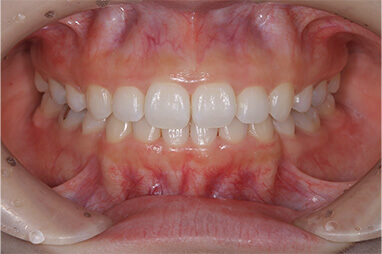

上の前歯の古い被せ物を治したいと言うことで来院されました。上下の前歯は少しガタガタになっており、奥歯には古い金属の詰め物が見られます。

上の前歯の被せ物が長い期間保つようにするためには、下の前歯のガタガタを整えておく必要があります。この症例くらいのガタガタであれば、インビザラインGoを使えば短期間で綺麗に治すことができます。歯並びが整ったことで治療のモチベーションが上がり、ホワイトニングと奥歯の銀歯を全てセラミックに置き換える治療を行い、金属がない(ノンメタル)状態になりました。